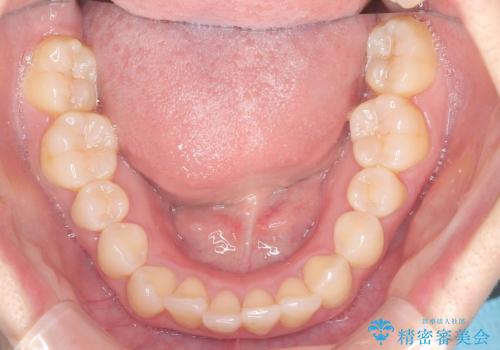

銀歯の下の虫歯|オールセラミッククラウン

担当医 河野豊嘉

奥歯に虫歯があると言われた セラミッククラウンでキレイで長持ちする歯へ

担当医 榊原康平